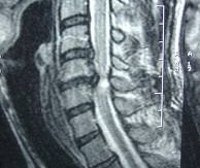

Детальное неврологическое исследование помогает неврологу выявить признаки поражения спинного мозга и определить уровень его локализации. Для более точной диагностики причин развития миелопатии необходима консультация ортопеда или вертебролога. Рентгенография позвоночника при дискогенной миелопатии определяет характерные для остеохондроза сужения межпозвонковых щелей, появление по краям позвонков остеофитных разрастаний. Для определения уровня и степени компрессии спинного мозга пациентам с дискогенной миелопатией проводят миелографию. С целью визуализации грыжи диска и исключения других причин развития миелопатии применяют МРТ позвоночника и КТ позвоночника.